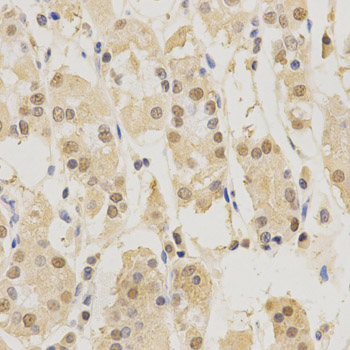

Immunohistochemistry of paraffin-embedded human stomach using PSMB5 antibody.